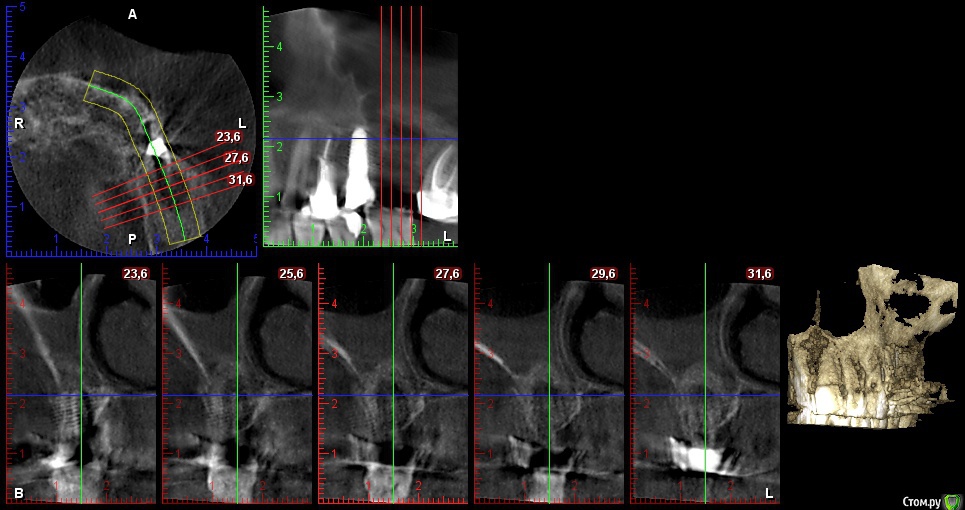

gum Опубликовано 31 января, 2018 Автор Поделиться Опубликовано 31 января, 2018 Сделали КТ, качество не очень хорошее. По клинике жалоб нет, не отслоился от мед стенки (понимаю, что ошибка, но на сколько критично?) плюс пазуха отреагировала утолщением слизистой.Подскажите как дальше вести пациента? Ссылка на комментарий